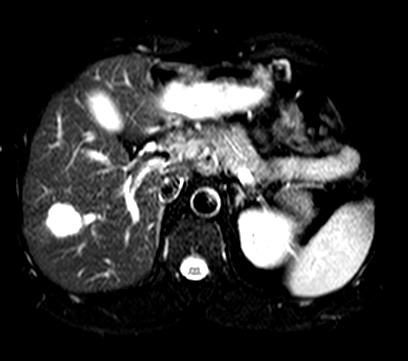

标题: CT19720:肝右叶血管瘤。肝左叶内侧段病灶考虑什么? [打印本页]

标题: CT19720:肝右叶血管瘤。肝左叶内侧段病灶考虑什么?

男,48岁,肝区不适月余,伴隐痛。

支持右叶血管瘤,左叶病灶考虑肝腺瘤。

1)不排除肝左叶肝癌。2)肝右叶血管瘤。

肝左叶炎性病变,肝癌待排。2)肝右叶血管瘤。

1.肝右叶血管瘤;2.肝左叶炎性假瘤?肝癌?建议穿刺活检.

右叶病灶典型,左叶病变慢性炎块

1、肝右叶血管瘤(典型)。

2、肝左叶病灶,强化不明显,疑炎性假瘤,建议结合临床并密切随访。

1、肝左叶炎性病变,肝癌待排。

2、肝右叶血管瘤。

肝左叶脓肿,肝癌待排。2)肝右叶血管瘤